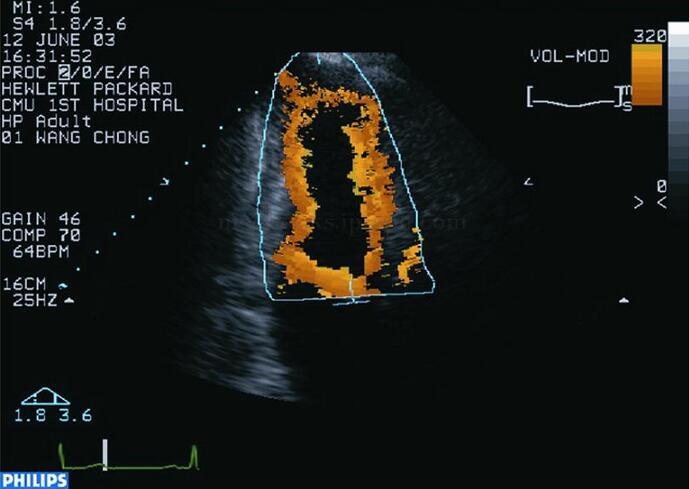

彩色室壁运动技术自动实时识别和跟踪血液与组织界面,以彩色梯度表示(图2‐1‐152,图2‐1‐153),其优点是直观、快速,缺点是受二维图像质量和人为操作误差的影响较大。

图2‐1‐152 正常人心尖两腔心切面彩色室壁运动技术(CK)舒张期显像

图2‐1‐153 正常人心尖两腔心切面CK技术收缩期显像